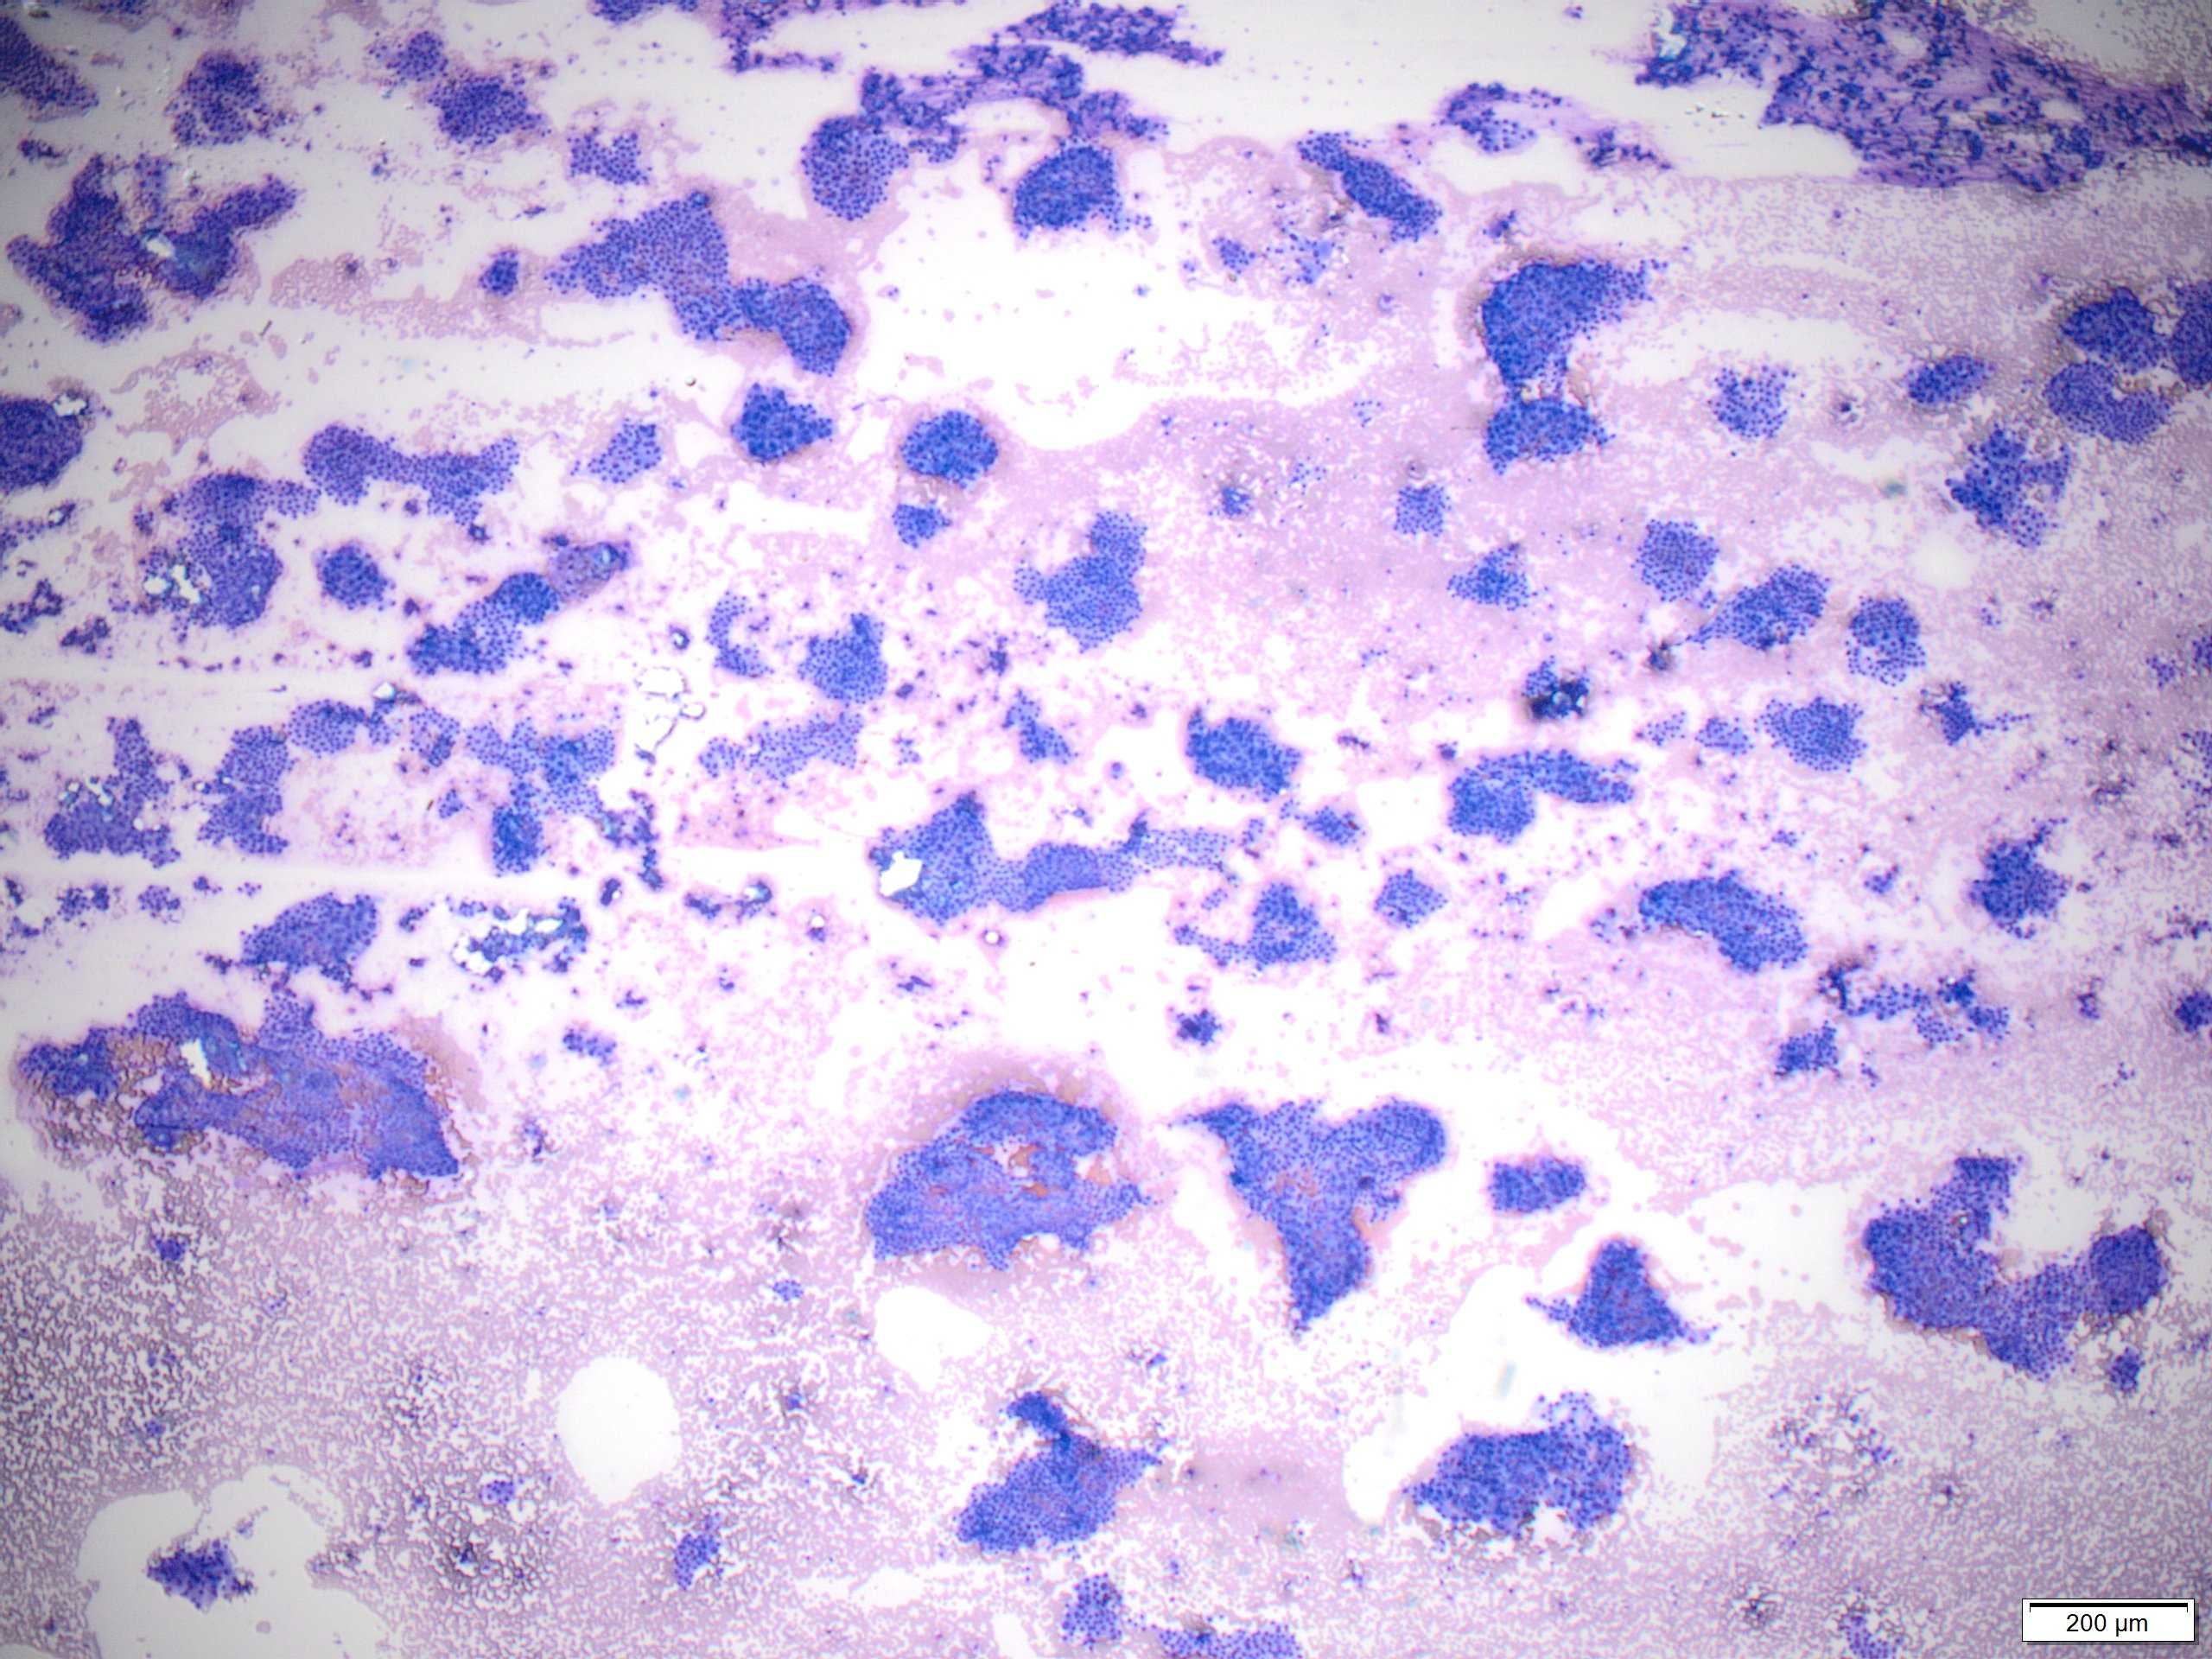

PTC is the most common thyroid malignancy in the United States. It can happen at any age with a female to male ratio of 3:1. The smear are usually cellular with sheets of follicular cells exhibiting nuclear overlapping and/or molding. The cytoplasm can be scant or abundant [squamoid, oncocytic (Picture #2) or vacuolated]. Intranuclear pseudoinclusions (black arrow) are specific to PTC and represent cytoplasmic invaginations. Other non-specific nuclear features include grooves (blue arrow) and nucleoli. Another highly specific feature is the presence of papillae with fibrovascular cores (Picture #3).